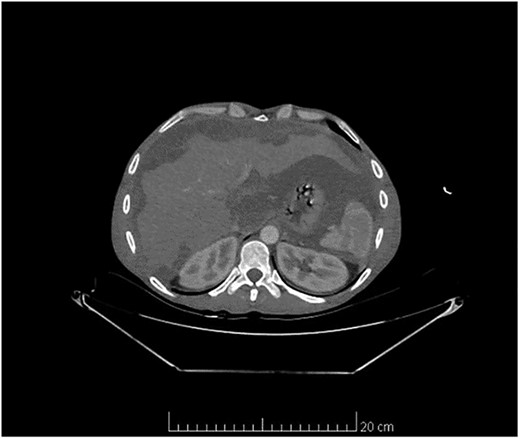

Computed tomography scan of the abdomen and pelvis showed massive amount of free abdominal fluid and irregular margins of the liver (Fig. 1).

Computed tomography scan of the abdomen and pelvis showed massive amount of free abdominal fluid and irregular margins of the liver.